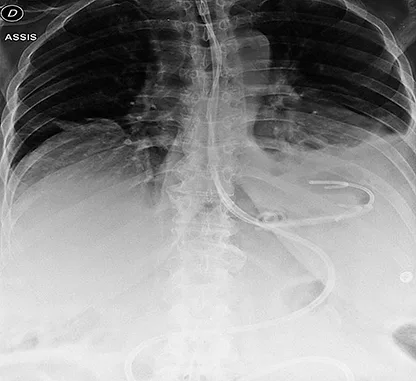

- Fistule de petite taille (< 20 mm). Le drainage interne par QDC est le traitement le plus couramment proposé à ce type de fistule. Les QDC sont habituellement laissées en place 4 semaines, un scanner de réévaluation est ensuite réalisé. Une nutrition entérale exclusive est souvent proposée pendant cette période, pour exclure la fistule et favoriser l’apport nutritionnel (figure 4). Certains centres autorisent une alimentation orale pendant la période de drainage interne. En cas d’évolution favorable, les QDC sont retirées lors d’une nouvelle endoscopie dans les semaines qui suivent. En cas d’évolution non favorable sur le scanner de contrôle, une nouvelle endoscopie pour amélioration du drainage interne est réalisée.

Figure 4 : Drainage interne par QDC après SG : 2 QDC et 1 drain nasocavitaire dans la fistule, sonde de nutrition entérale